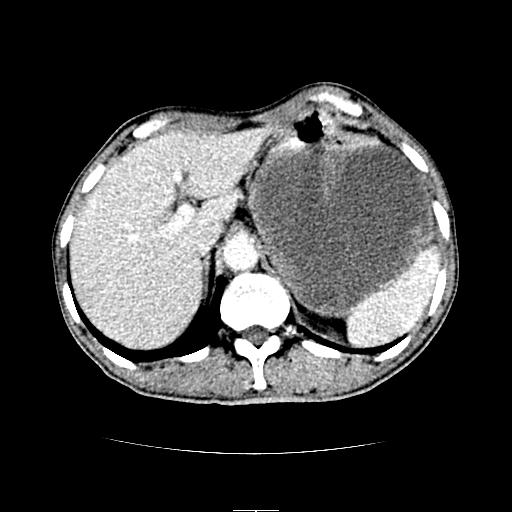

左上腹胃、脾及胰腺间巨大囊性占位性病变,内见多数薄隔,有轻度强化,明显占位效应。左肾见一小囊肿。

考虑:1、左上腹巨大囊肿(可能来源于胰腺)。

2、左肾小囊肿。

左上腹胃、脾及胰腺间巨大囊性占位性病变,内见多数薄隔,有轻度强化,明显占位效应,胰腺及左肾结构清楚,明显向后下方推压 移位。左肾见一小囊肿.多考虑:1 网膜巨大囊肿。2 左肾小囊肿。

1胃脾胰之间一巨大囊性影,胃明显向前推移,胰体尾部似肥大,考虑囊性影来源于胰腺(假性囊肿?)2左肾小囊肿。

左上腹囊性占位,与胰腺分界不清,考虑起源于胰腺可能。

左上腹囊性占位,虽与胰腺分界不清,胰尾似乎受压前移,病灶最大截面并不在胰腺水平,考虑来源于网膜可能性大吧,应再详细追问病史.

左上腹胃、脾及胰腺间巨大囊性占位性病变,其内见多数薄隔,有轻度强化,明显占位效应。左肾见一小囊性变。

左肾囊肿;网膜巨大囊肿。